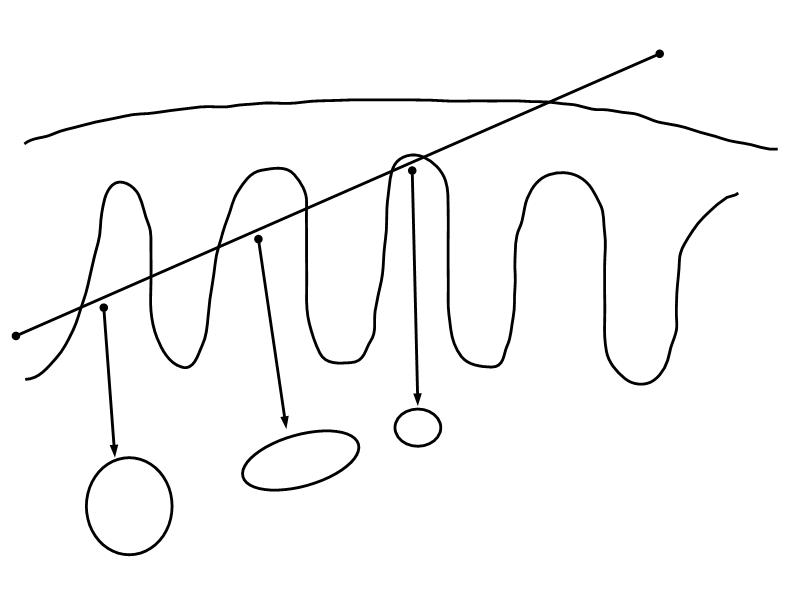

Mammary gland

Write short notes describing the structure of the mammary gland.

(5)

Mammary gland

- Compound tubuloalveolar gland

- 12 - 20 glands

- Each with own lactiferous duct

- Each with own lactiferous sinus

- Opens on skin at apex of nipple

Two stages

- Resting

- Active

Resting and active

Describe the resting mammary gland and compare with the active gland.

(8)

Resting gland

- Connective tissue dominate

- More adipose tissue

- Glandular tissue reduced

Active gland

- Terminal ducts expand

- Forms alveoli

- Connective tissue reduced

- Adipose tissue reduced

- Glandular tissue dominate